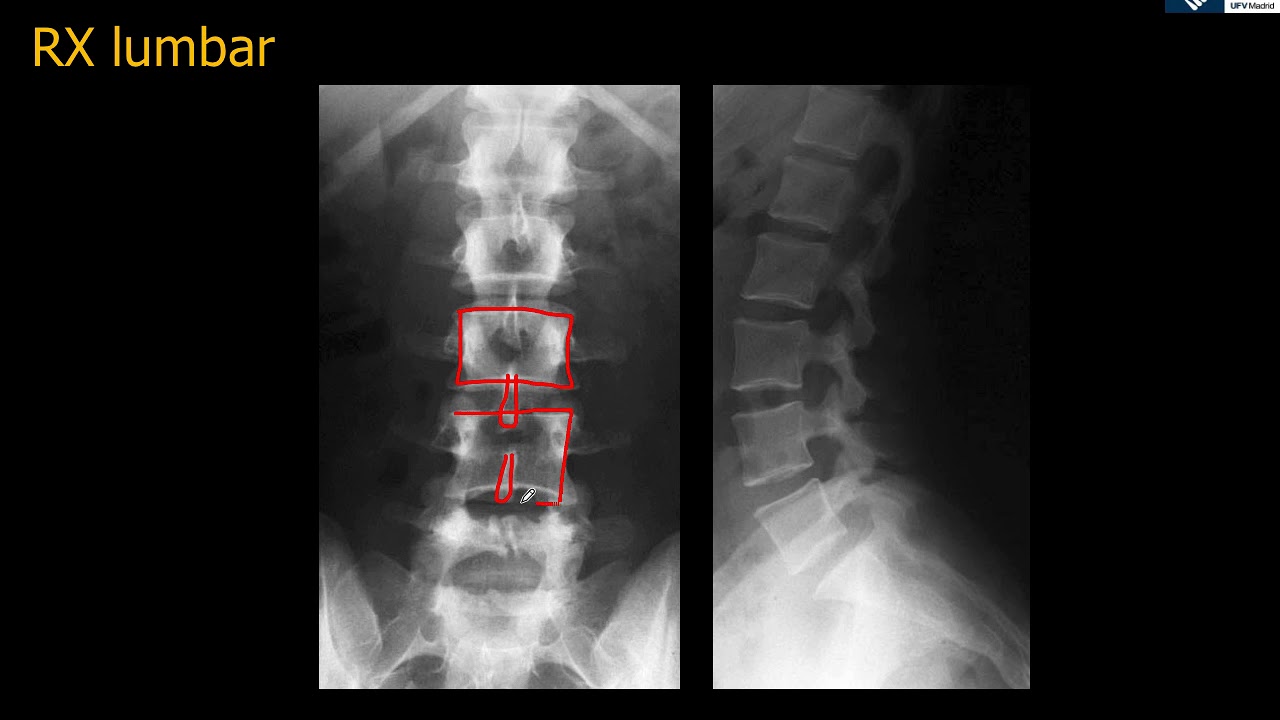

WebLa radiografía de columna lumbar se realiza para evaluar la columna vertebral en la zona lumbar. Se puede utilizar para diagnosticar problemas de la. WebUna radiografía de la columna lumbosacra es una imagen de los pequeños huesos (vértebras) en la parte baja de la columna. Esta zona incluye la región lumbar y el. WebEn la radiografía de columna lumbar lateral se harán evidentes la calcificación y la osificación de los ligamentos longitudinal anterior y posterior, signo de espondilitis. WebLas radiografías de la columna lumbosacra pueden mostrar: Curvas anormales de la columna vertebral. Desgaste anormal del cartílago y huesos de la región lumbar, tales.

WebLa radiografía funcional de la columna lumbar se realiza en la proyección lateral. El paciente está de pie, tocando de lado el soporte vertical de rayos X. Primero,. WebLas “manchas en los pulmones” son opacidades o densidades “blanquecinas” que se ven en la radiografía o TAC de tórax y pueden deberse a distintas. WebRadiografía o rayos X: son buenos para mostrar huesos y grandes estructuras internas, pero no son buenos para mostrar problemas con los “tejidos blandos”. Los tejidos. WebUna radiografía es una prueba rápida e indolora que genera imágenes de las estructuras internas del cuerpo, en especial de los huesos. Los haces de rayos X. WebTomografía computerizada. La tomografía computerizada (TC) es una técnica muy útil para evaluar las anomalías anatómicas de la columna lumbosacra. Ofrece imágenes de. Web¿Que se ve en una radiografía de la columna? La radiografía de la columna se realiza para detectar y diagnosticar lesiones de los huesos, articulaciones y tejidos.

Clase de Anatomía radiológica de la región lumbar